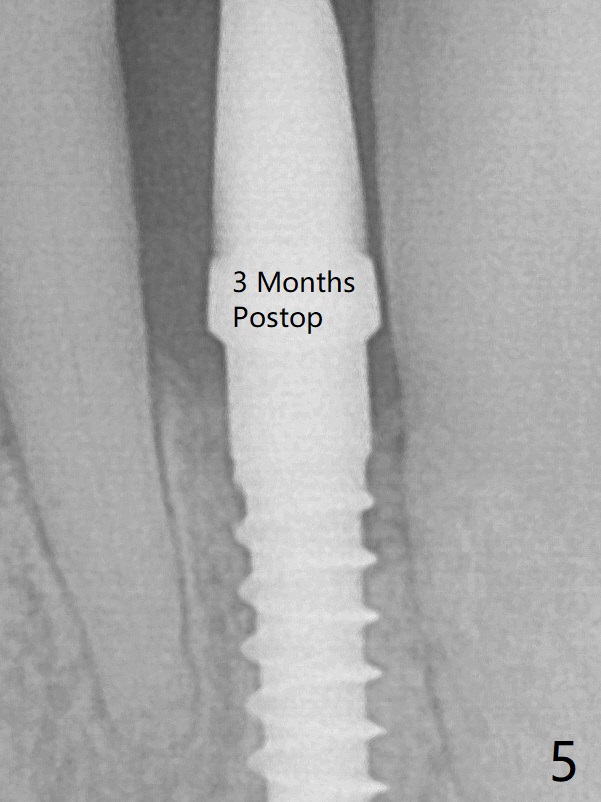

The gingival depth is measured 2-4 mm after extraction. The 1st intraop PA taken with 1.2 mm drill for 16 mm shows the mesiodistal width is 5.11 mm (Fig.2); a 2.5x14(2) mm 1-piece implant is placed with >35 Ncm (Fig.3 with allograft placed). There is no bone loss 3 months postop (Fig.5). The distal crest seems to be reduced in density and lower in height 1 year 7 months (Fig.7) and 1 year 11 months (Fig.8) post cementation. The severity does not worsen probably related to use of water pik.